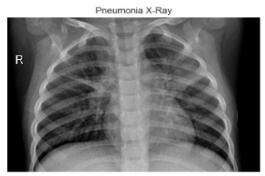

Fig-1:NormalCXRImages Fig-2:PneumoniaAffectedCXRImages